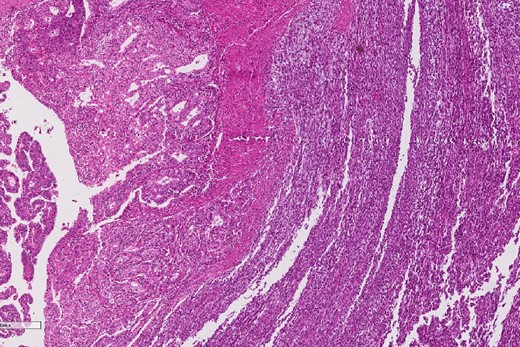

A review of the previously resected esophageal tumor revealed the presence of both epithelial and sarcomatous components. The epithelial component was composed of moderately to poorly differentiated adenocarcinoma, while the sarcomatous component showed hyperchromatic round to spindle cells with scant cytoplasm and frequent mitoses (Figs 3–6). The intrathoracic tumor showed a similar morphology as the sarcomatous component of the esophageal tumor, with focal rhabdomyoblastic differentiation (Fig. 7). The latter was strongly positive for desmin, myogenin, and MyoD1 and was focally positive for synoplastin, CD56, CD 10, and FL1.

High power magnification of the esophageal tumor showing the adenocarcinoma intermixed with spindle cell sarcoma.